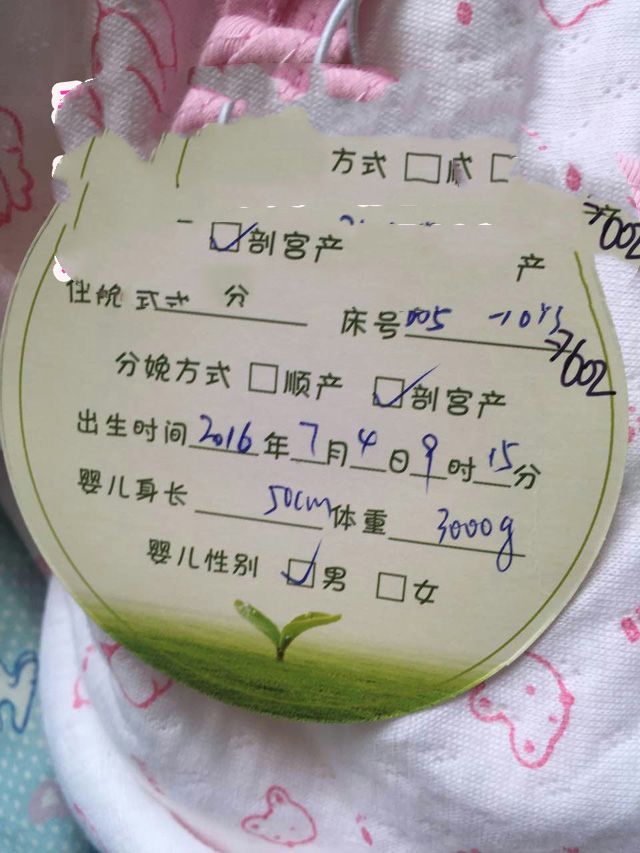

2016年7月4日,孕37周,男宝宝顺利降临。